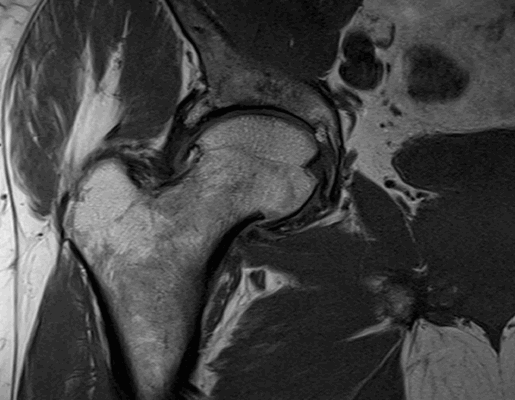

Импиджмент синдром на МР-фото

К механическому конфликту между бедренной головкой/шейкой и краем вертлужной впадины приводят одно- или двусторонние дефекты костей врожденного или приобретенного генеза. Видоизмененные компоненты сочленения вызывают дисфункцию конечности за счет соударения во время движения. Патологическое трение костей способствует разрастанию остеофитов на фоне постоянной травматизации вертлужной губы. Если своевременно не диагностировать заболевание и не начать лечение, последняя с течением времени разорвется., Хрящевая ткань сочленяющих костей будет разрушена. Подобный механический конфликт часто способствует формированию коксартроза и сопровождается прогрессирующим болевым синдромом.

МРТ тазобедренного сустава при феморо-ацетабулярном импинджмет-синдроме показывает возможные причины заболевания: